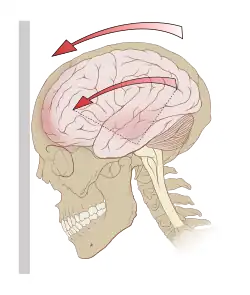

Concussão é um dano nas funções cerebrais após um traumatismo craniano. Caracteriza-se pela presença de sintomas neurológicos sem nenhuma lesão identificada, mas com danos microscópicos, dependendo da situação, reversíveis ou não.[1][2]

A concussão cerebral é a perda da consciência de curta duração, que acontece logo após um traumatismo craniano (bater com a cabeça).

Diferente da contusão, as concussões causam uma disfunção cerebral temporária, sem apresentar fratura do crânio ou feridas na cabeça. Elas podem ocorrer mesmo após um traumatismo crânio-encefálico menor, dependendo da intensidade com que o cérebro foi mobilizado no interior da caixa craniana.